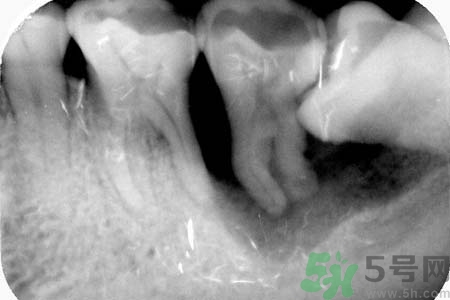

長(zhǎng)智齒疼痛怎么辦?長(zhǎng)智齒牙齦腫了怎么辦?

長(zhǎng)智齒疼怎么辦?長(zhǎng)智齒是一件讓人很頭疼的事情,智齒疼起來(lái)真是要人命,不少長(zhǎng)過(guò)智齒的人都有這種體驗(yàn)。關(guān)于長(zhǎng)智齒疼痛怎么辦?長(zhǎng)智牙齦齒腫了怎么辦?小編為您一一解答。

5、如果智齒經(jīng)常疼,而且疼的比較厲害,可能已經(jīng)引發(fā)牙冠周軟組織發(fā)炎,所以導(dǎo)致智齒腫脹、疼痛;再如果智齒長(zhǎng)的位置很歪,影響其它牙齒正常咀嚼,也影響美觀,最好是考慮拔牙。拔牙前提是確保牙冠周?chē)鷽](méi)有炎癥,才能安排拔牙,免除后顧之憂,拔智齒是拔牙里最難的一種,所以一定要到正規(guī)口腔醫(yī)院,請(qǐng)正規(guī)醫(yī)師進(jìn)行專(zhuān)業(yè)拔牙。

6、如果智齒經(jīng)常疼,而且疼的比較厲害,可能已經(jīng)引發(fā)牙冠周軟組織發(fā)炎,所以導(dǎo)致智齒腫脹、疼痛;再如果智齒長(zhǎng)的位置很歪,影響其它牙齒正常咀嚼,也影響美觀,最好是考慮拔牙。拔牙前提是確保牙冠周?chē)鷽](méi)有炎癥,才能安排拔牙,免除后顧之憂,拔智齒是拔牙里最難的一種,所以一定要到正規(guī)口腔醫(yī)院,請(qǐng)正規(guī)醫(yī)師進(jìn)行專(zhuān)業(yè)拔牙。